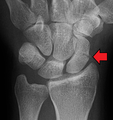

A subtle scaphoid fracture

A more obvious scaphoid fracture on a scaphoid view X ray